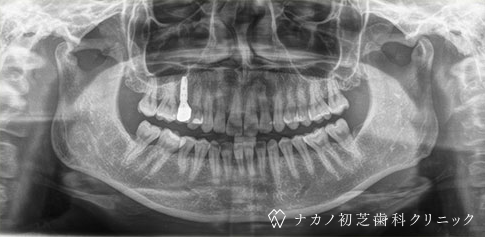

インプラント・13本 (60代女性)

BEFORE

AFTER

年齢 60代女性

治療内容 インプラント治療13本(骨造成の併用)

インプラント治療とは、歯を抜いた所にチタン製の人工歯根を埋入し、その上に歯を入れる方法です。骨を増やすことで、より審美的に治療が出来ました。費用 1本 400,000円(税込 440,000円)

リスク・副作用

腫れ・疼痛・違和感を感じるなどの症状を生じることがあります。